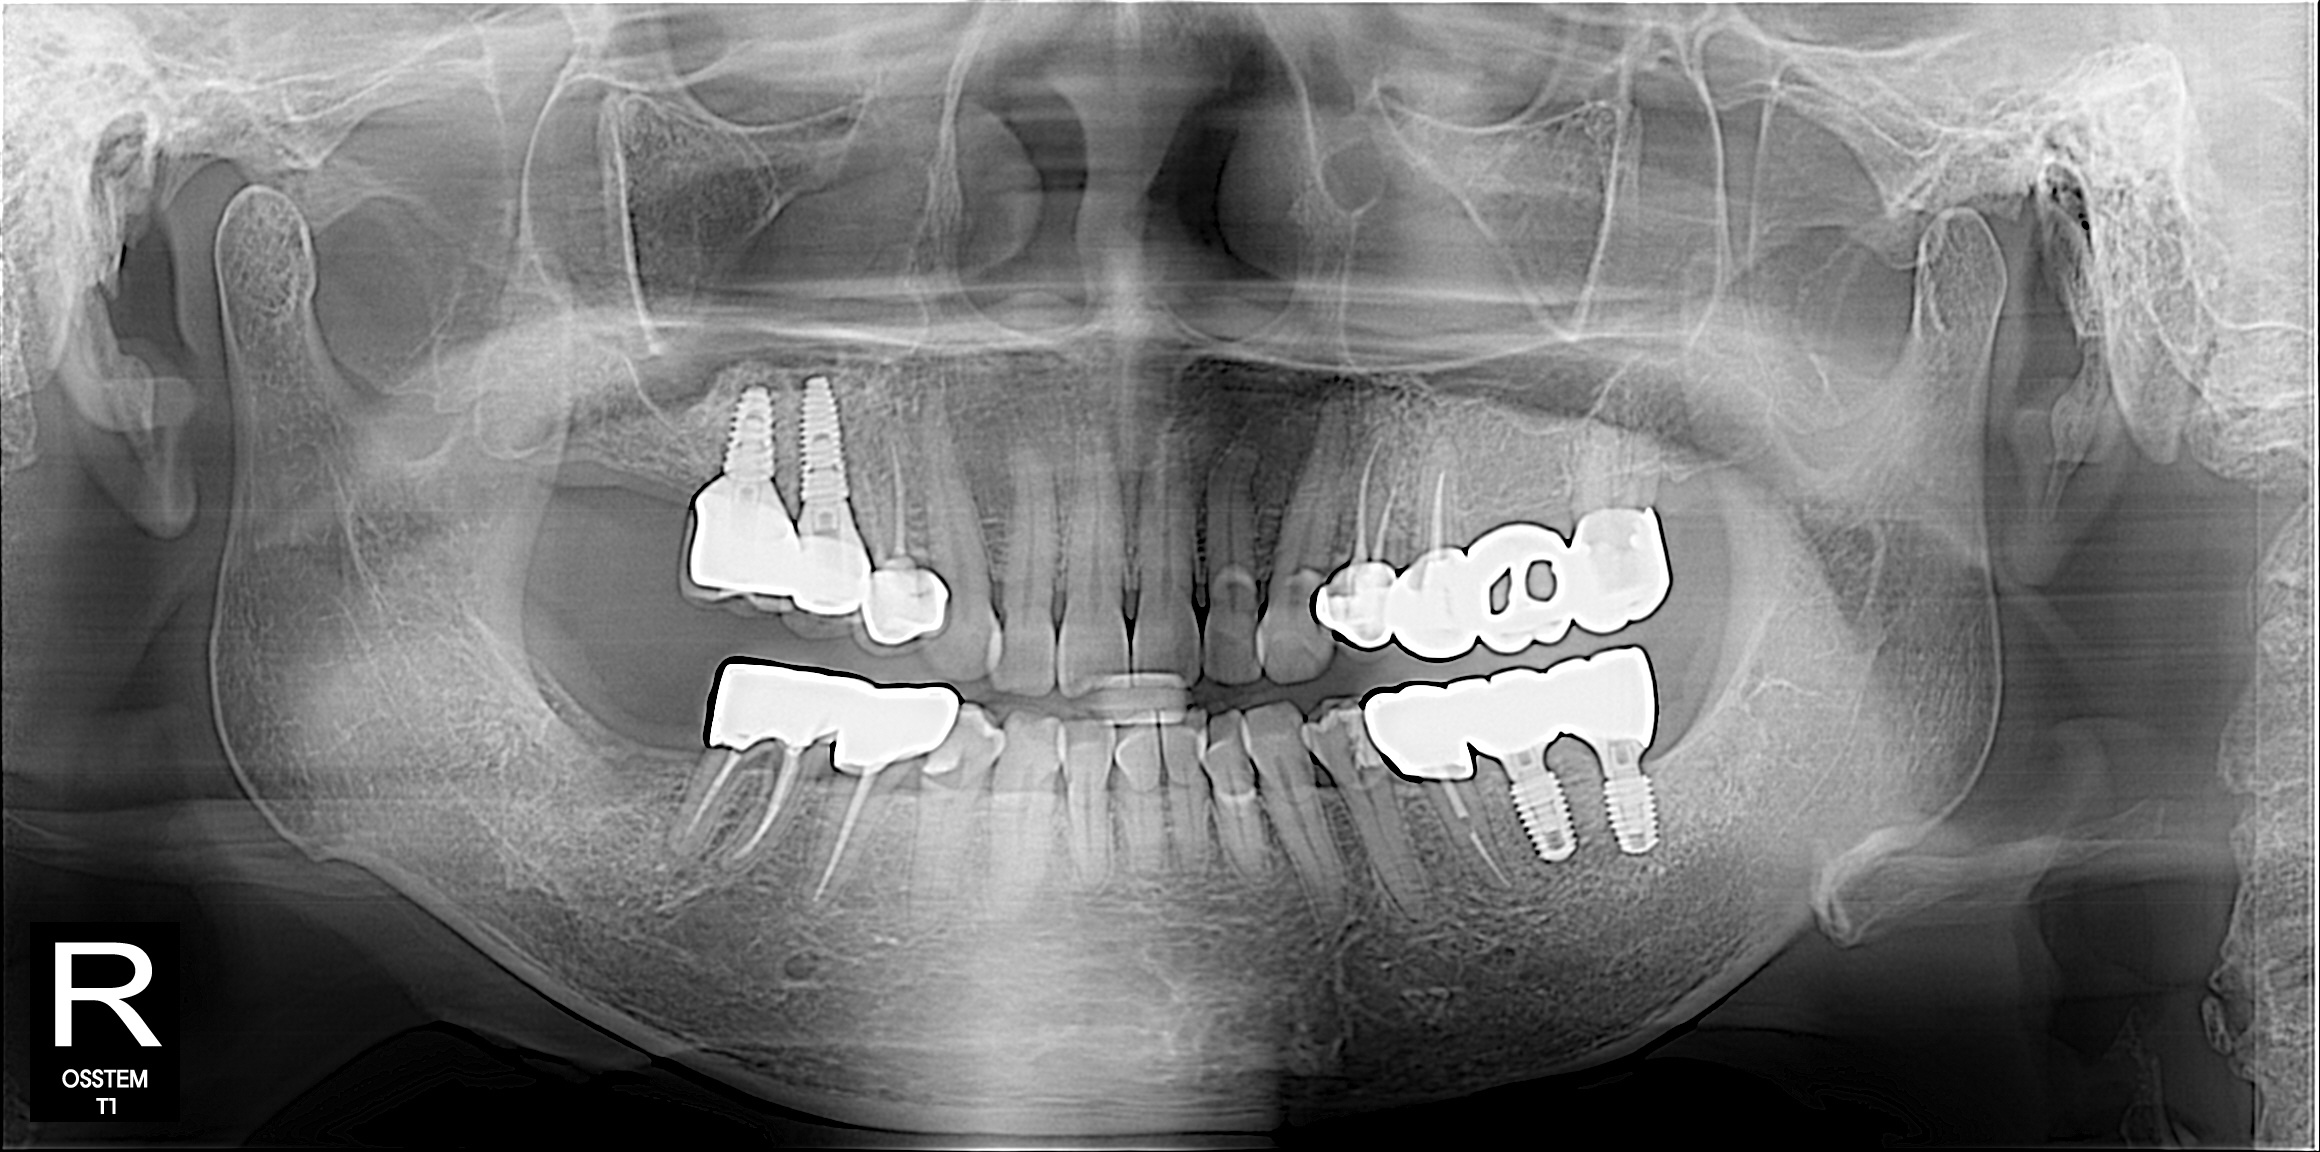

결과로 증명하는

치료케이스

상담부터 사후관리까지

환자 한 분, 한 분의 상태에맞춰 꼼꼼하게 진행합니다.

임플란트

BEFORE & AFTER